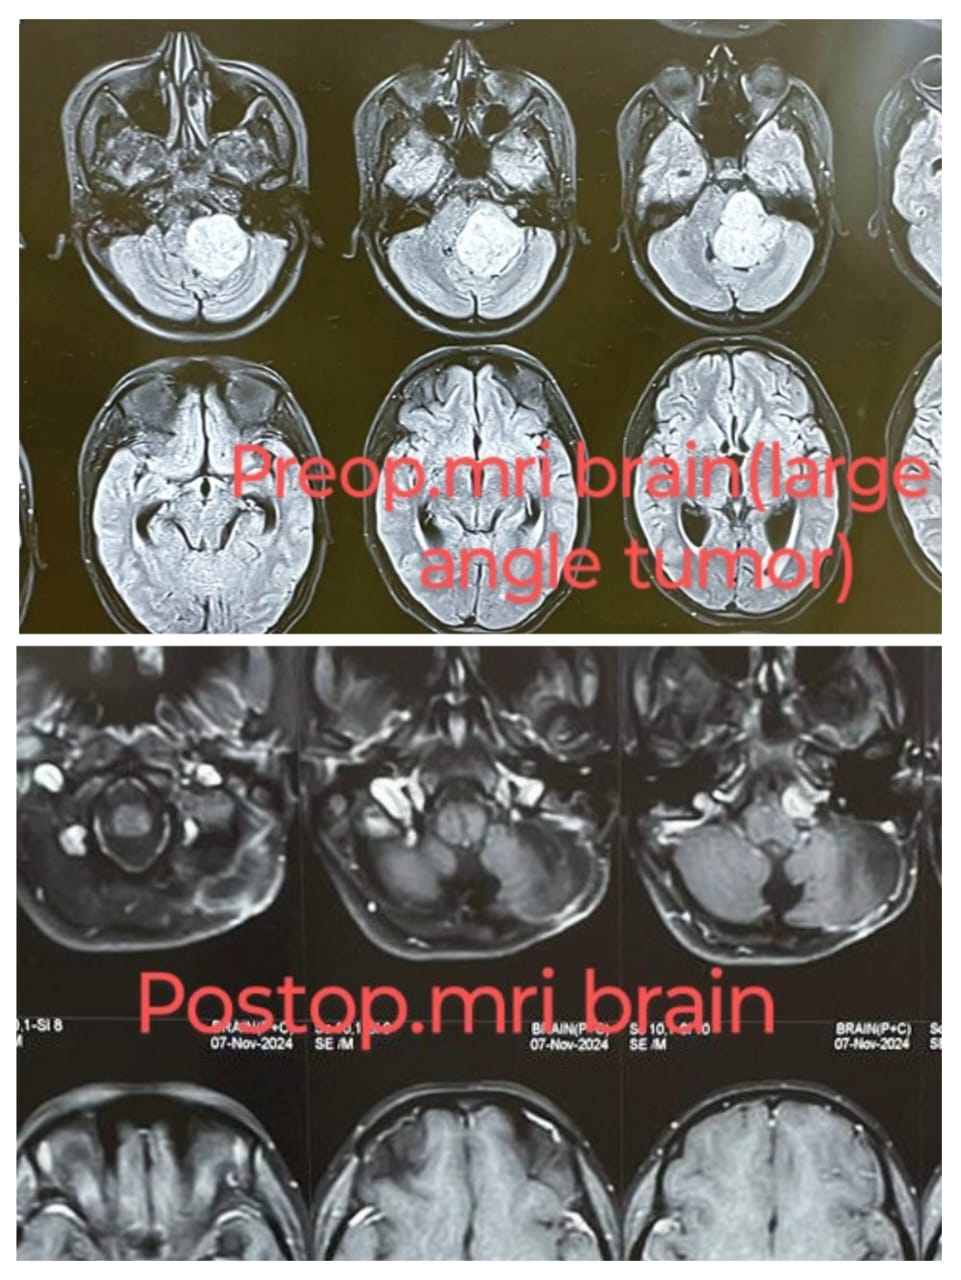

Preoperative & Postoperative MRI

Before and after surgery comparison using MRI imaging.

This case demonstrates a large cerebellopontine (CP) angle tumor seen clearly in the preoperative MRI scans. Post-surgical MRI shows significant reduction in tumor size with preserved surrounding neural structures.

Such tumors, often vestibular schwannomas or meningiomas, are managed surgically with great care to avoid damage to adjacent nerves and brainstem. This case resulted in a favorable outcome.